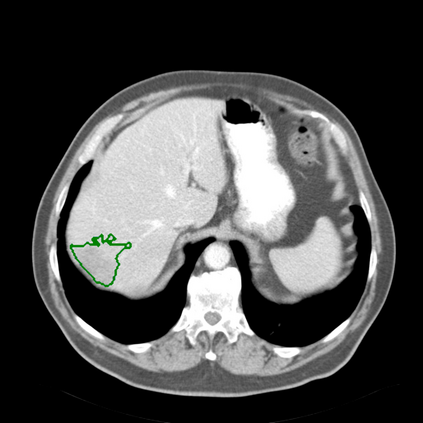

Radiomics uses quantitative medical imaging features to predict clinical outcomes. Currently, in a new clinical application, finding the optimal radiomics method out of the wide range of available options has to be done manually through a heuristic trial-and-error process. In this study we propose a framework for automatically optimizing the construction of radiomics workflows per application. To this end, we formulate radiomics as a modular workflow and include a large collection of common algorithms for each component. To optimize the workflow per application, we employ automated machine learning using a random search and ensembling. We evaluate our method in twelve different clinical applications, resulting in the following area under the curves: 1) liposarcoma (0.83); 2) desmoid-type fibromatosis (0.82); 3) primary liver tumors (0.80); 4) gastrointestinal stromal tumors (0.77); 5) colorectal liver metastases (0.61); 6) melanoma metastases (0.45); 7) hepatocellular carcinoma (0.75); 8) mesenteric fibrosis (0.80); 9) prostate cancer (0.72); 10) glioma (0.71); 11) Alzheimer's disease (0.87); and 12) head and neck cancer (0.84). We show that our framework has a competitive performance compared human experts, outperforms a radiomics baseline, and performs similar or superior to Bayesian optimization and more advanced ensemble approaches. Concluding, our method fully automatically optimizes the construction of radiomics workflows, thereby streamlining the search for radiomics biomarkers in new applications. To facilitate reproducibility and future research, we publicly release six datasets, the software implementation of our framework, and the code to reproduce this study.

翻译:放射科使用定量医学成像特征来预测临床结果。目前,在一个新的临床应用中,通过一个超常试验和高压过程,通过人工操作,从广泛的现有选项中找到最佳放射法。在本研究中,我们提议了一个框架,自动优化每个应用程序的放射工作流程的建设。为此,我们将放射作为模块工作流程,并包括每个部件的大量通用算法。为了优化每个应用程序的工作流程,我们使用随机搜索和聚合的自动机学习方法。我们用12种不同的临床应用来评估我们的方法,结果在曲线下应用的以下领域:1) 脂色瘤(0.83);2) 脱氧型纤维瘤(0.82);3 初级肝脏肿瘤(0.80);4 气肠肿瘤(0.77)、5 彩虹肝脏移植(0.61); 6 脑膜细胞变异常(0.45); 7) 肝细胞变异常(0.8) 脑纤维变异位(0.80); 9) 直径直线型癌症(0.74) 和头型癌症(0.77) 直径研究(10) 。